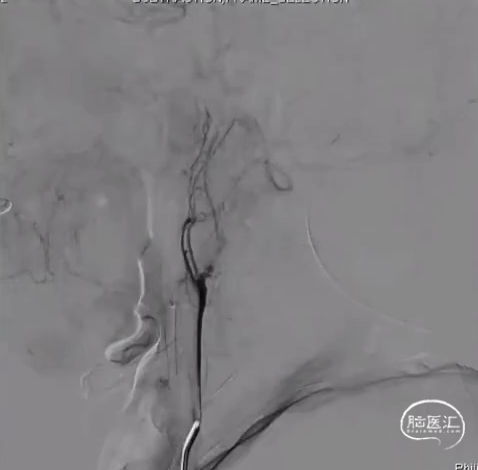

术前DSA R-CCA

球囊由远及近扩张

Xpert支架植入